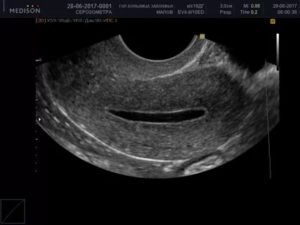

Чтобы выявить скопление жидкости, обязательно ультразвуковое обследование. Только оно способно точно определить серозометру.

Что делать, для обнаружения патологии? Существует ряд заболеваний, которые по своей симптоматике очень похожи между собой. Для выявления серозометры используются такие методы диагностики, как УЗИ и гинекологический осмотр.